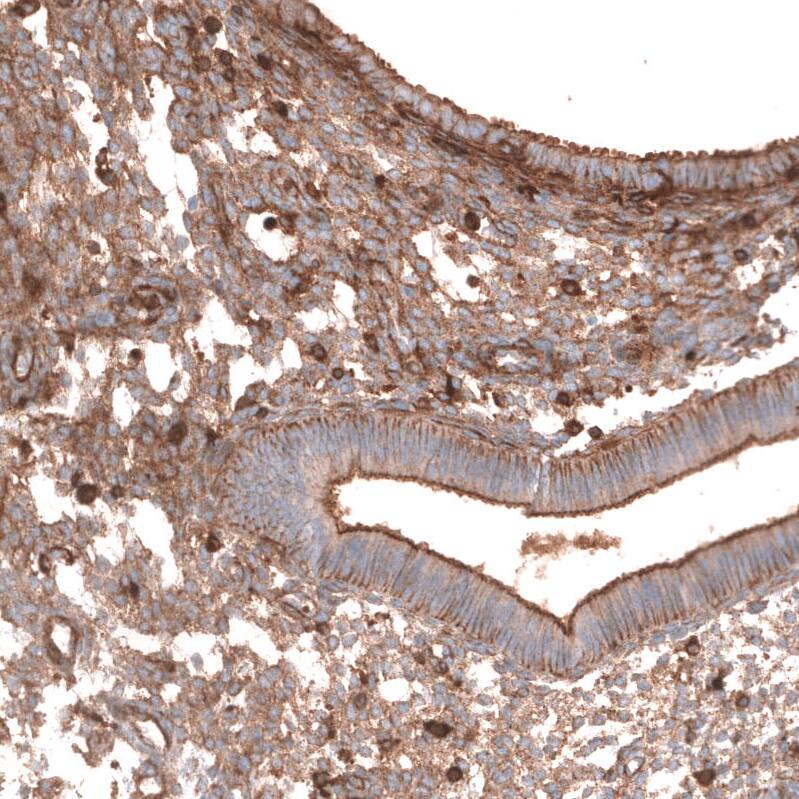

Staining of human endometrium shows moderate membranous positivity in glandular cells and endometrial stromal cells.